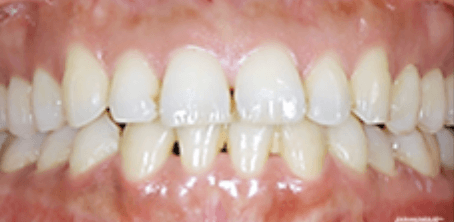

治療後

治療前後の比較